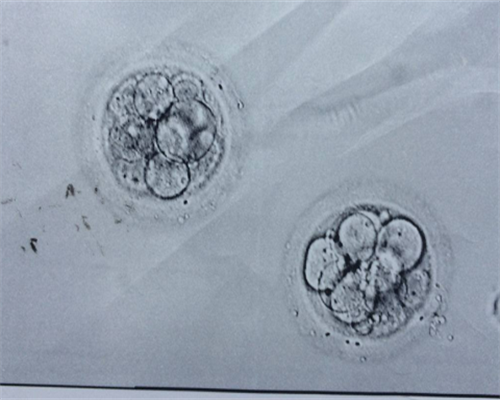

实验室操作费用: 包括取卵、胚胎培养、胚胎移植等实验室操作费用。其中,胚胎培养的费用在 3000 元左右,取卵和胚胎移植的费用在 2000 元左右。